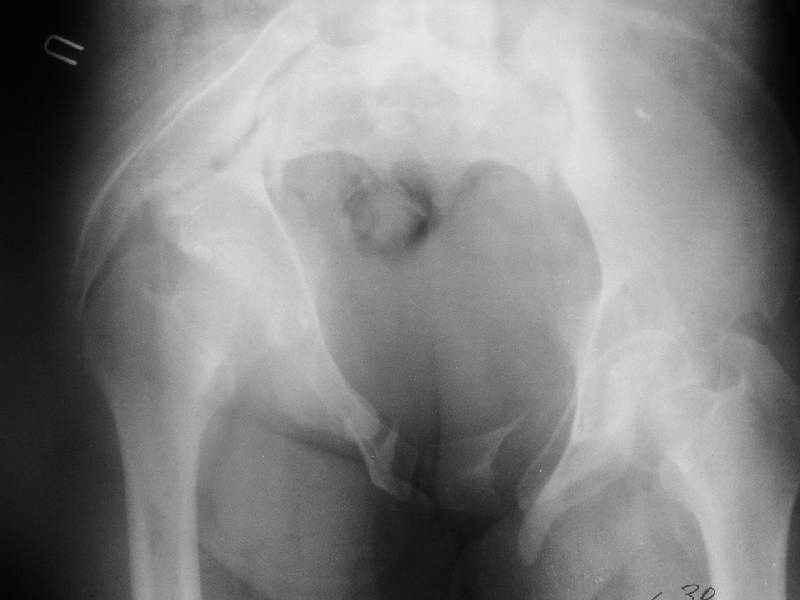

Снимки до лечения: